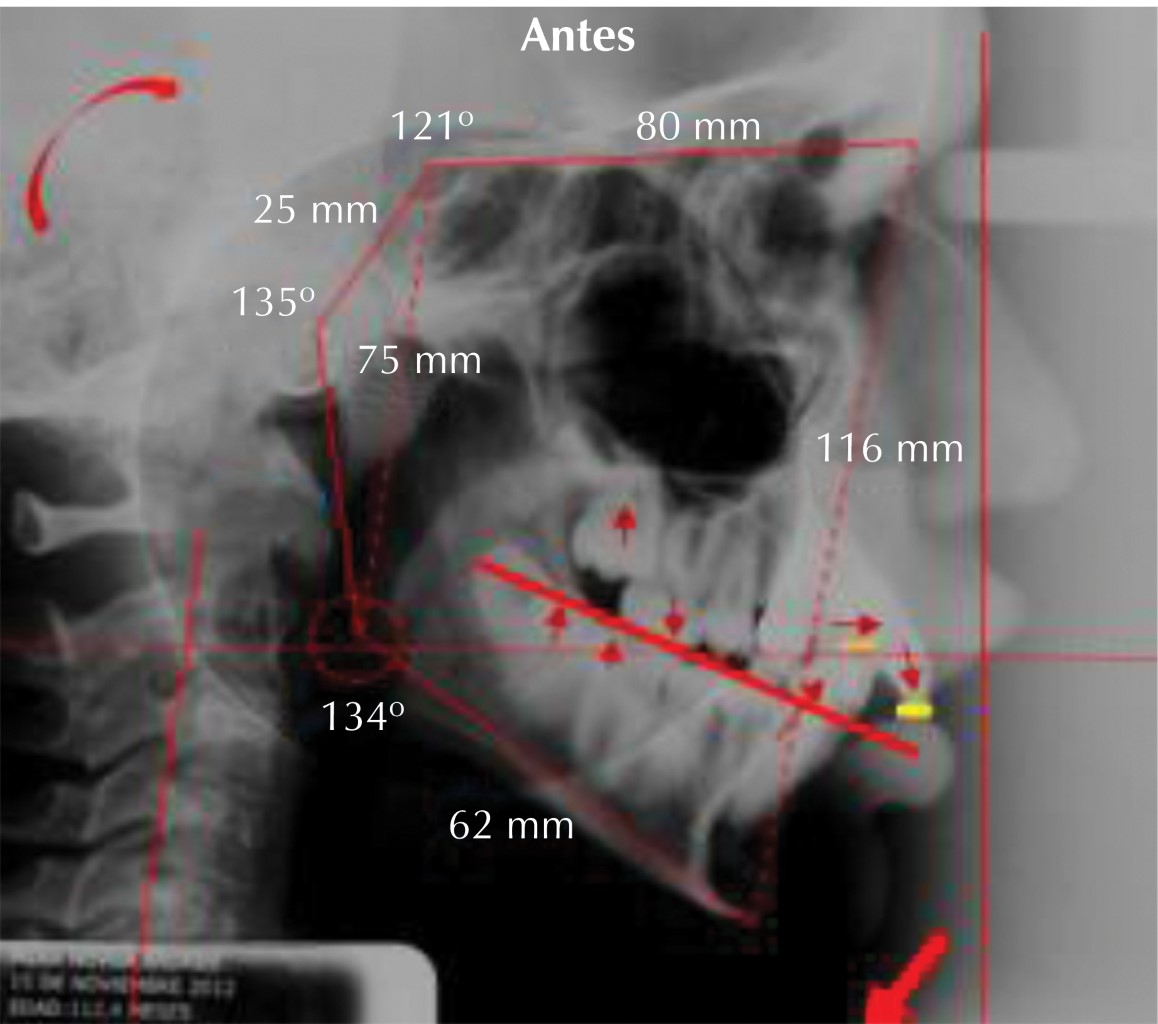

Paciente con antecedentes de problemas respiratorios, hiperdivergente, clase II esquelética, plano oclusal inclinado, perfil convexo, apiñamiento dental superior e inferior, clase II molar, incompetencia labial severa de 11 mm, mordida profunda anterior de 8 mm, mentón retrusivo -17 mm, posterorotación mandibular, plano mandibular inclinado, ángulo goníaco alto en relación a horizontal verdadera-stomion superior (Sts), antero rotación de cabeza, cervicales rectificadas, espacio entre C0 y C1 aumentado, espacio en C2 y C3 muy reducido5,6 (Figuras 1, 2, 3 y 4).

La corrección de un plano oclusal inclinado en niños y adolescentes hiperdivergentes con tendencia a palanca tipo 2, sobre todo con problemas respiratorios y maloclusiones verticales; mejora de manera importante el vector de crecimiento, el desarrollo en la altura del ángulo goníaco y la proyección del mentón al corregirlo y hacerlo más horizontal con las mecánicas ortodóncicas al corregir la inclinación del plano oclusal al hacerlo más horizontal y tratar de que coincida en lo posible con la línea horizontal-stomion superior (línea roja punteada); por lo tanto, en el presente caso clínico sí existe una correlación entre la corrección de la inclinación del plano oclusal y el desarrollo de la altura del ángulo goníaco, longitud de la rama mandibular (inicial 45 mm y final 51 mm), mayor proyección del mentón, al hacer el plano oclusal más horizontal con la presente mecánica ortodóncica mediante extracciones, curvas inversas y manejo de plano oclusal1,5,7,8,10,11 (Figura 9).

Figura 2